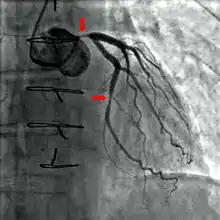

Coronary angiography of a critical sub-occlusion of the common trunk of the left coronary artery and the circumflex artery. (See arrows)

During coronary catheterization (often referred to as a cath by physicians), blood pressures are recorded and fluoroscopy (X-ray motion picture) shadow-grams of the blood inside the coronary arteries are recorded. In order to create the X-ray pictures, a physician guides a small tube-like device called a catheter, typically ~2.0 mm (6-French) in diameter, through the large arteries of the body until the tip is just within the opening of one of the coronary arteries. By design, the catheter is smaller than the lumen of the artery it is placed in; internal (intra-arterial) blood pressures are monitored through the catheter to verify that the catheter does not block blood flow (as indicated by "dampening" of the blood pressure).

A coronary angiogram (an X-ray with radiocontrast agent in the coronary arteries) that shows the left coronary circulation. The distal left main coronary artery (LMCA) is in the left upper quadrant of the image. Its main branches (also visible) are the left circumflex artery (LCX), which courses top-to-bottom initially and then toward the centre/bottom, and the left anterior descending (LAD) artery, which courses from left-to-right on the image and then down the middle of the image to project underneath the distal LCX. The LAD, as is usual, has two large diagonal branches, which arise at the centre-top of the image and course toward the centre/right of the image.